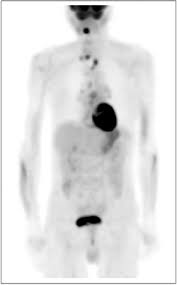

Tobacco is the single greatest cause of preventable death globally.[3] Tobacco use leads most commonly to diseases affecting the heart, liver and lungs, with smoking being a major risk factor for heart attacks, strokes, chronic obstructive pulmonary disease (COPD) (including emphysema and chronic bronchitis), and cancer (particularly lung cancer, cancers of the larynx and mouth, and pancreatic cancer). It also causes peripheral vascular disease and hypertension. The effects depend on the number of years that a person smokes and on how much the person smokes. Starting smoking earlier in life and smoking cigarettes higher in tar increases the risk of these diseases. Also, environmental tobacco smoke, or secondhand smoke, has been shown to cause adverse health effects in people of all ages.[4] Cigarettes sold in underdeveloped countries tend to have higher tar content, and are less likely to be filtered, potentially increasing vulnerability to tobacco-related disease in these regions.[5]

Smoke contains several carcinogenic pyrolytic products that bind to DNA and cause many genetic mutations. There are 45 known or suspected chemical carcinogens in cigarette smoke.[9] Tobacco also contains nicotine, which is a highly addictive psychoactive drug. When tobacco is smoked, nicotine causes physical and psychological dependency. Tobacco use is a significant factor in miscarriages among pregnant smokers, and it contributes to a number of other threats to the health of the fetus such as premature births and low birth weight and increases by 1.4 to 3 times the chance for Sudden Infant Death Syndrome (SIDS).[10] The result of scientific studies done in neonatal rats seems to indicate that exposure to cigarette smoke in the womb may reduce the fetal brain's ability to recognize hypoxic conditions, thus increasing the chance of accidental asphyxiation.[11] Incidence of impotence is approximately 85 percent higher in male smokers compared to non-smokers,[12] and is a key factor causing erectile dysfunction (ED).[12][13][14]